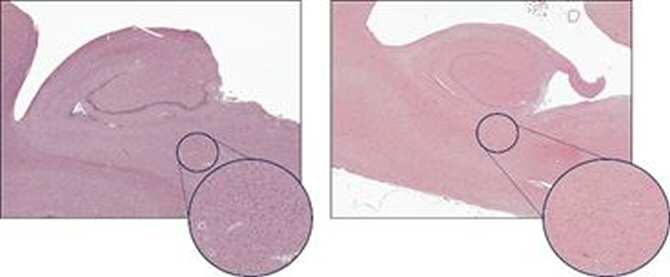

La esclerosis del hipocampo (EH) vista al microscopio. A la izquierda, un hipocampo sin EH (estadio 0) y a la derecha, uno afectado por EH avanzada (estadio IV). Fijándose en el círculo, se puede apreciar la pérdida masiva de neuronas (marcadas en azul) con la EH. (Imágenes: UPM)

Para entender mejor esta patología, el equipo de investigación evaluó muestras cerebrales de pacientes con demencia pertenecientes a la cohorte Alzheimer de Vallecas – Centro Alzheimer Fundación Reina Sofía (CAV-CAFRS). Este es un proyecto singular, desarrollado por la Fundación CIEN con el apoyo y equipamiento de la Fundación Reina Sofía, que permite estudiar la trayectoria clínica de pacientes con demencia que donan generosamente su cerebro al Banco de Tejidos de la Fundación CIEN. Bajo el microscopio, los investigadores han observado cambios asociados a fases tempranas de la esclerosis del hipocampo y han conseguido establecer un sistema para evaluar su severidad. Este sistema reveló importantes diferencias clínicas, ya que los pacientes en estadios más avanzados de la enfermedad presentaban un peor estado cognitivo. Además, analizando imágenes de resonancia magnética del cerebro de estos pacientes, se pudo comprobar que esta clasificación también reflejaba cambios en la estructura cerebral asociados a esta patología.

Estos resultados dieron pie a un trabajo posterior en el que se utilizaron datos de seguimiento de neuroimagen de estos pacientes. Los investigadores analizaron resonancias obtenidas durante más de una década, y detectaron que los cambios estructurales asociados a la esclerosis del hipocampo estaban presentes más de 11 años antes de su observación al microscopio. Hasta el momento, esta patología se entendía como una lesión tardía, presente en personas muy mayores, ya que solo podía evaluarse tras la muerte. Los resultados de esta investigación permiten comprender la duración de esta enfermedad durante la vida de los pacientes, lo que podría servir para su detección temprana.